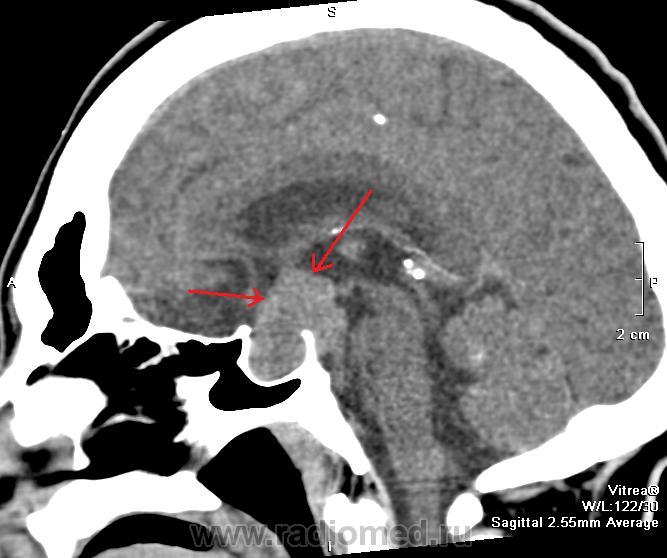

Аденома гипофиза. Образование в просвете слегка растянутого турецкого седла (красные стрелки), распространяющиеся над седлом до третьего желудочка (зеленая стрелка). Черная стрелка - спинка турецкого седла. Аденома растет и кзади от спинки турецкого седла, влево от седла. Следовательно образование не только интраселлярное, но и супра-, пара-, ретроселлярное. Клиника типичная - акромегалия, головные боли, нарушение зрения.